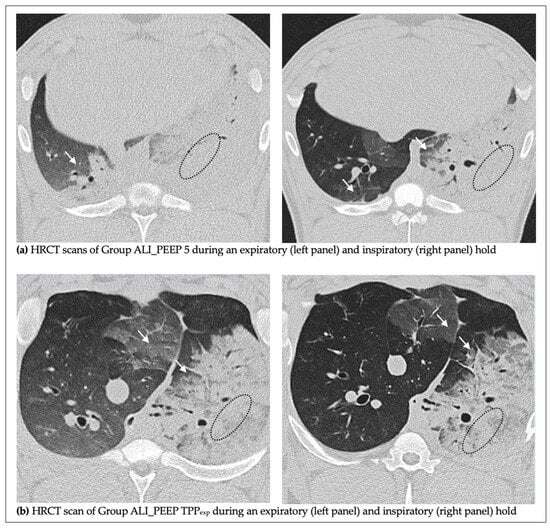

2.2. High-Resolution Computed Tomography Lung Injury Score

2.2.1. Left vs. Right Lung

2.2.2. Expiratory vs. Inspiratory Hold

2.2.3. ALI_PEEP 5 vs. ALI_PEEP TPPexp

3.3. HRCT Findings

4.4. Induction of Unilateral Acute Lung Injury

4.8. Histological Analysis